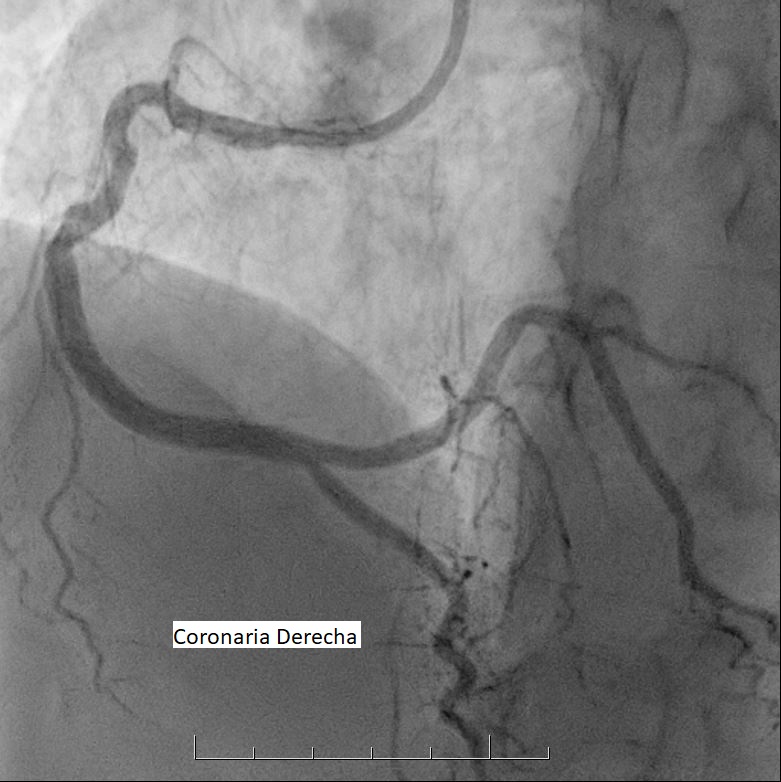

La sala donde te realizarán el estudio se encuentra a baja temperatura. Este procedimiento se efectúa con anestesia local y comienza con la introducción de un catéter por punción en una de las arterias de la muñeca o la ingle, de acuerdo a las características de cada persona.

Este catéter llega hasta las arterias coronarias y una vez allí se inyecta una sustancia de contraste, que permite visualizarlas y verificar si hay obstrucciones.

Es posible que luego de este estudio los médicos determinen apropiado realizar una angioplastía para tratar las obstrucciones. Te comunicarán la situación a vos y a tu familia. En este caso, deberás tener en cuenta que la angioplastía puede requerir una internación de 24 horas en la Unidad de Cuidados Intensivos Cardiológicos. Para más información sobre este tratamiento, te recomendamos que leas el contenido Angioplastia Coronaria (desde acá).